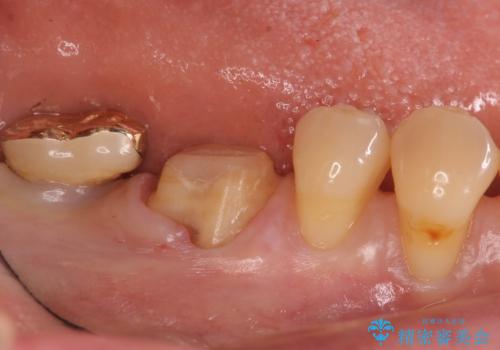

- 昔つめた材料が欠けたこと、歯の捻転を主訴に来院されました。

矯正治療の希望はなかったため、被せ物で歯の形を修正することになりました。

不適合だった詰め物の裏側に大きな虫歯がありました。

セラミックインレーやアンレーでは強度に不安が残るため、クラウンでの修復処置としました。

クラウンでは歯のがたつきを修正することもできます。

虫歯の除去と歯の捻転の両方を解決することができました。